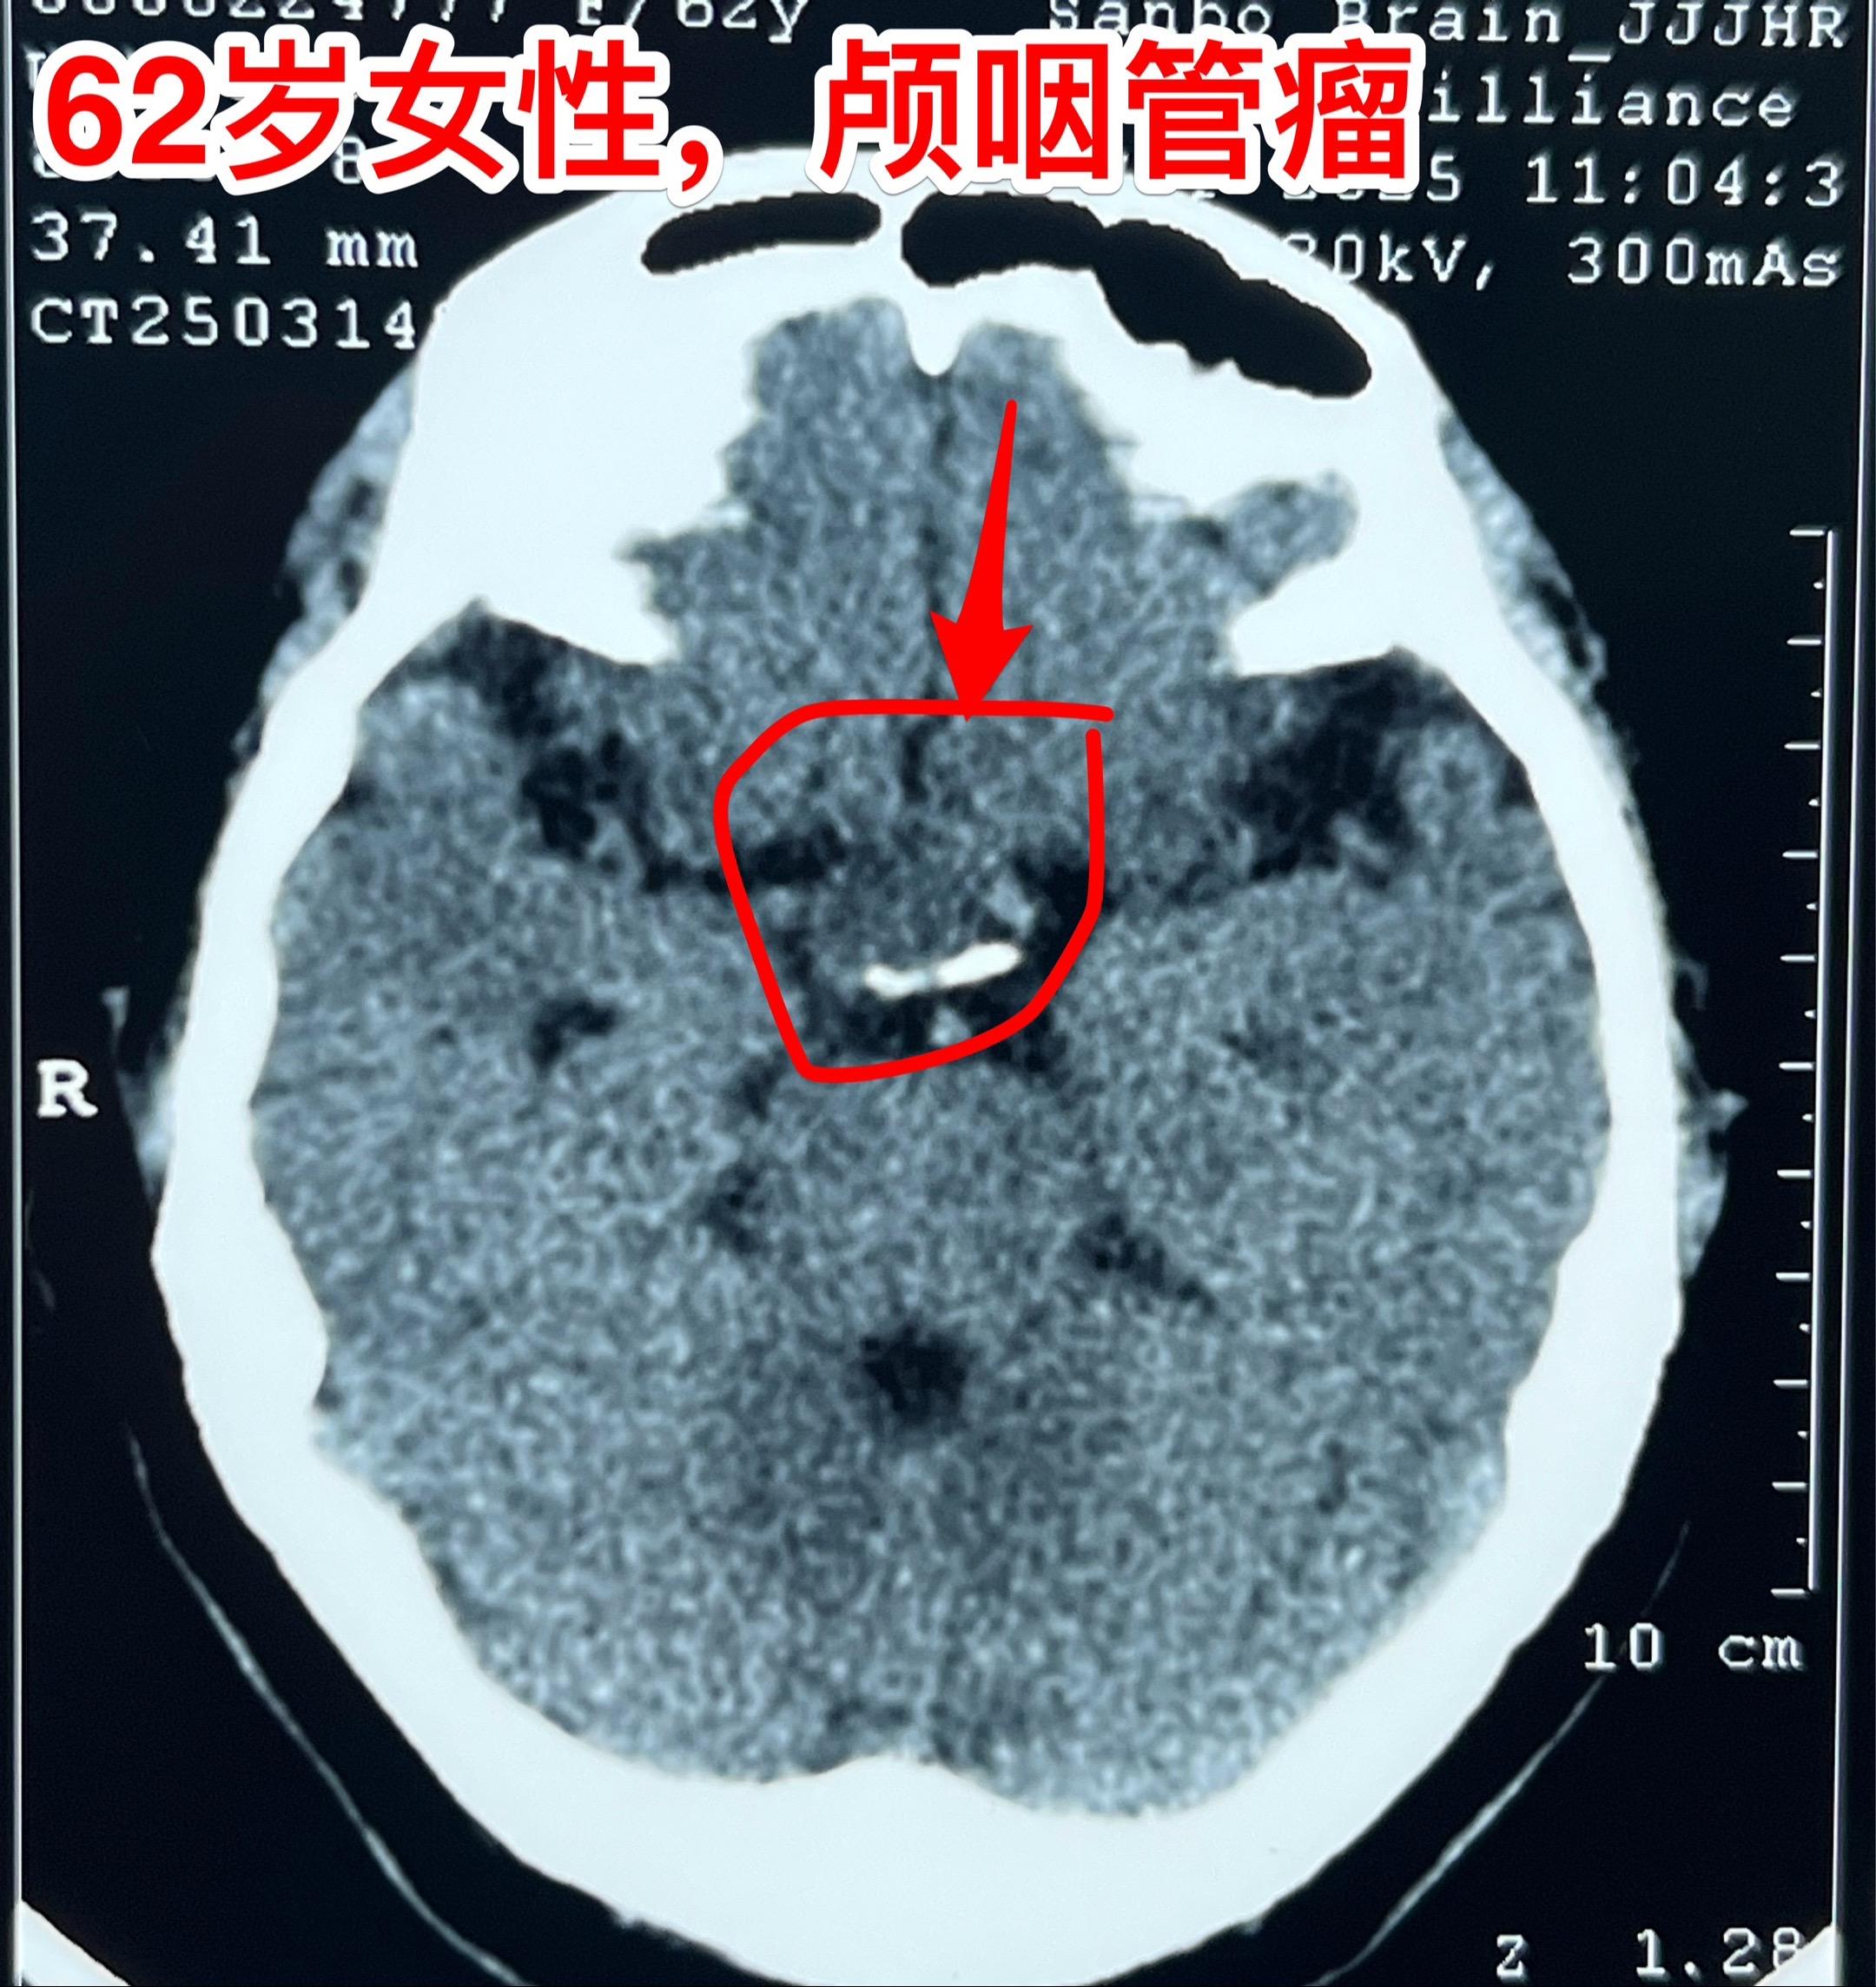

经翼点入路切除颅咽管瘤-不能忘记的入路 经翼点入路切除颅咽管瘤,曾经是广泛使用的一种入路,当然有其优点。近十几年使用这个入路切除颅咽管瘤的机会大大减少了。 对于比较小的鞍上型颅咽管瘤或者自中线偏向侧裂池方向生长的颅咽管瘤,这个入路是很适合的。 3月21日为62岁女性病人切除颅咽管瘤,采用的就是经翼点入路。肿瘤得到完全切除,垂体柄得到保护[强]